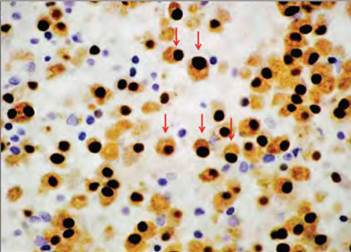

El paciente fue revisado por el servicio de hematología, se valoraron los estudios de laboratorio y RM, por la sospecha de MM y se practicó aspirado de médula ósea que mostró 60% de células plasmáticas anormales (Figura 1), por lo que inició tratamiento médico a base de talidomida más dexametasona, dabigatrán y recibió su primera dosis de ácido zoledrónico, además se solicitaron estudios de extensión en búsqueda de lesiones en otras regiones con una serie ósea metastásica (Figura 4).